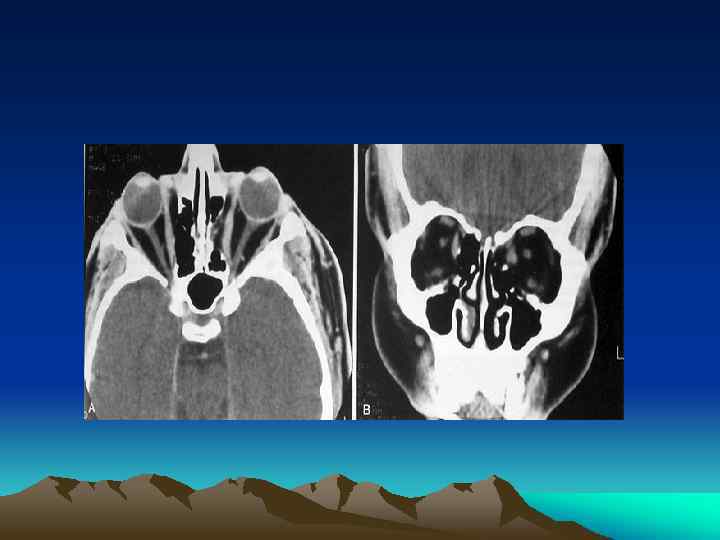

Facial Plain Films Ø Largely been replaced by computer tomography (except for the mandible) Plain Film Mandible Series and Panorex Computed Tomography (CT) Ø Most informative radiographic exam fro head and neck Trauma Ø Axial and coronal facial CT with bone and soft tissue window, 2 -3 mm sections

NASO-ORBITOETHMOID (NOE)FRACTURES

Introduction Ø Ø Ø NOE: frontal process of maxilla, nasal bones, and orbital space Sign& Symptoms Pseudohypertelorism (Traumatic Telecanthus)

Anatomy Ø Ø Medial Canthal Ligament (MCL) Lacrimal Collecting System Puncta Canaliculi Lacrimal Sac Lacrimal Duct

Management Ø First reconstruct medial orbital wall prior to repair of the MCL Ø Must consider associated injuries Ø May attempt closed reduction if MCL and lacrimal system is intact Ø Telescoping Nasal Bones and Frontal Process of the Maxilla